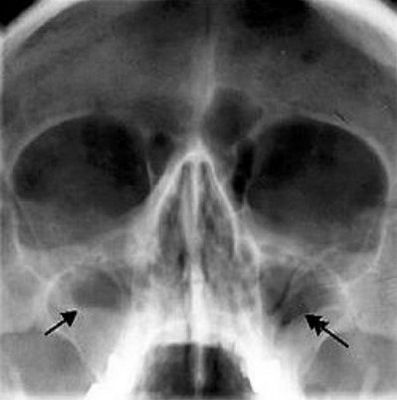

Острый гайморит — воспаление гайморовых пазух, которое может ухудшить качество жизни. Важно распознать его симптомы и причины, чтобы избежать осложнений

Верхнечелюстной синусит — воспалительное заболевание верхнечелюстных синусов, проявляющееся в острой и хронической формах. Многие пациенты принимают его